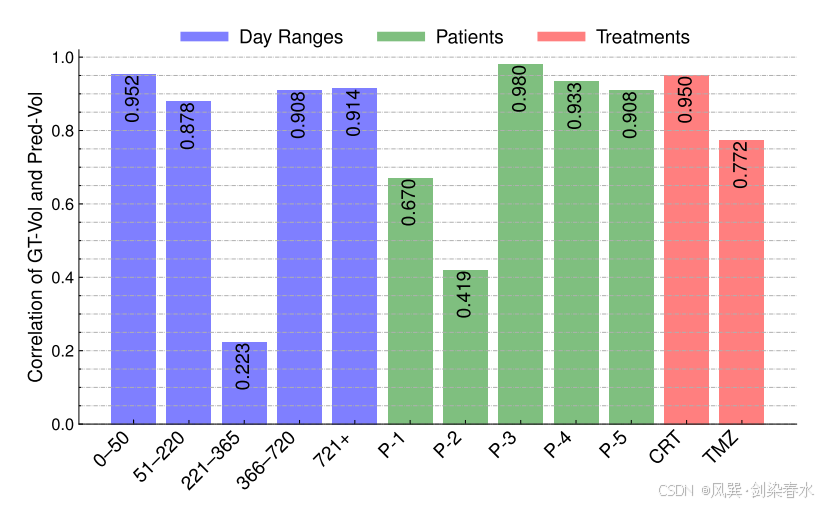

Figure 9 | 不同日期范围、患者和治疗类型之间 GT-Vol 和 Pred-Vol 的 Pearson 相关系数: